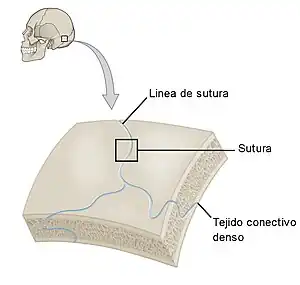

Son aquellas en que los extremos de los huesos están unidos por tejido fibroso. Este tipo de articulaciones tienen muy poca movilidad. Un ejemplo de articulación fibrosa son las suturas que unen los huesos del cráneo. Un tipo particular de articulación fibrosa es la sindesmosis en la que dos huesos se unen mediante una lámina de tejido fibroso, como ocurre en la membrana interósea del antebrazo que une el cúbito con el radio. Un caso particular es la sindesmosis dentoalveolar, también llamada gonfosis, que es una articulación fibrosa, sin movimiento en condiciones normales, que se establece entre la raíz de una pieza dental y la apófisis alveolar situada en la mandíbula.[7]

Las sinartrosis son articulaciones que tienen muy poca movilidad. Las uniones entre los huesos que forman el cráneo se llaman suturas y son un buen ejemplo de sinartrosis.[9] Dependiendo del tipo de tejido que sirve de unión, se dividen en:

- Sinfibrosis, cuando el tejido de unión es fibroso como en las suturas entre los huesos del cráneo.